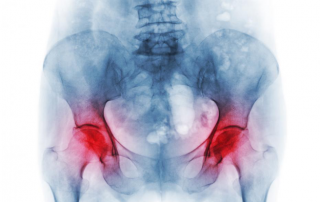

Osteoporosis is a condition characterized by loss of bone or [...]